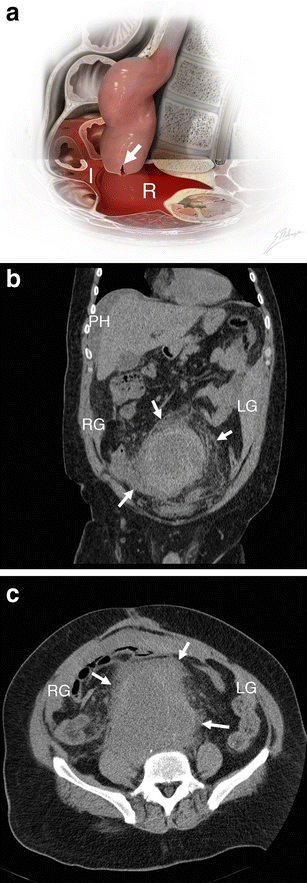

Intraperitoneal haematoma. a Illustration depicts AAA rupture of the left anterolateral wall (white arrow). Massive haemorrhage extends into both the retroperitoneal (R, shown as translucent red blood) and intraperitoneal (I, shown as more opaque blood) spaces. b Coronal unenhanced CT of a 51-year-old man demonstrates intraperitoneal haematoma involving the perihepatic space (PH), right (RG), and left (LG) paracolic gutters. Retroperitoneal haematoma (white arrows) is also seen. Attenuation of 60 HU indicates acute haemorrhage. c Axial unenhanced CT of the same patient shows right (RG) and left (LG) paracolic gutters, as well as retroperitoneal haematoma (white arrows)